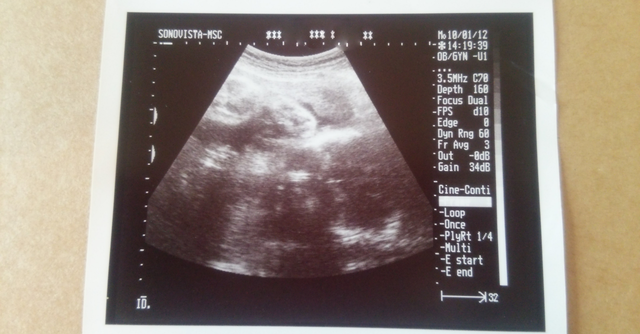

写真あり 妊娠10週目 エコー お腹の大きさと気をつけること こそだて情報局